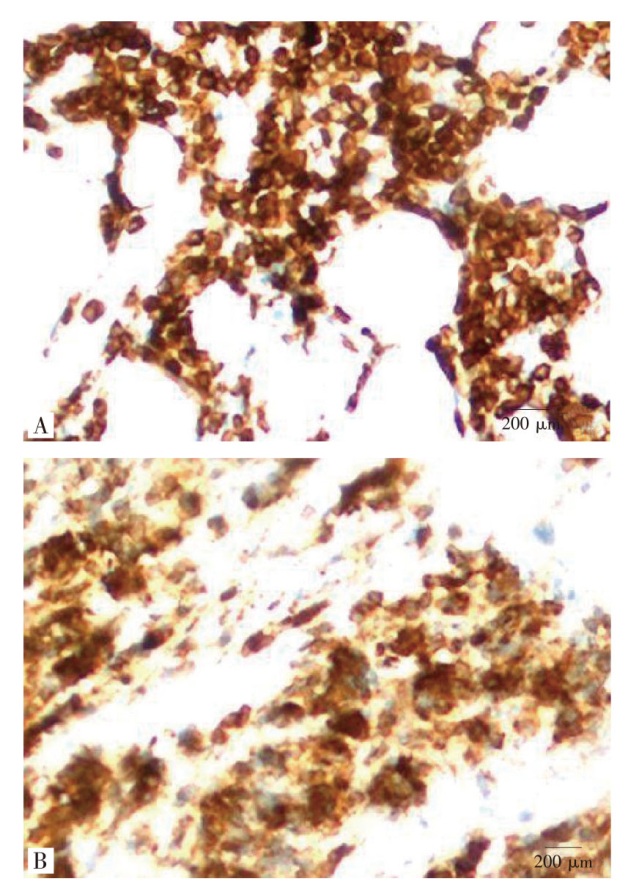

滤泡性淋巴瘤(follicular lymphoma,FL)是一种惰性进展的非霍奇金淋巴瘤,以数年的无痛性淋巴结肿大为典型特征,以腹水为主要症状较为少见,且这类患者实验室检查结果不典型,难以与其他腹膜转移性疾病鉴别。报告1例既往子宫内膜肿瘤且未遵医嘱完成化疗疗程,并在术后2个月失访的患者,因进行性腹胀就诊,超声显示腹腔内大量腹水,全腹增强CT报告腹膜后及肠系膜多发肿大淋巴结,腹膜及大网膜结节样增厚,腹水细胞学检查未见瘤细胞。行腹腔镜探查术,最终术后病理明确为FL,患者已完成6个周期利妥昔单抗+苯达莫司汀化疗,目前未见复发。当存在腹部恶性肿瘤病史患者出现腹膜病变时,尤其淋巴结肿大的情况下,即使影像学无法明确淋巴瘤,除考虑原发肿瘤转移外,需将血液系统肿瘤纳入鉴别诊断体系。

Follicular lymphoma (FL) is an indolent non-Hodgkin lymphoma characterized by painless lymph node enlargement over several years. It is relatively rare for FL to present with ascites as the main symptom. Moreover, the laboratory test results of such patients are often atypical, making it difficult to distinguish from other peritoneal metastatic diseases. This paper reports a case of a patient with a history of endometrial tumor who did not complete the chemotherapy course as prescribed and was lost to follow-up 2 months after surgery. The patient presented with progressive abdominal distension. Ultrasound showed a large amount of ascites in the abdominal cavity. Enhanced CT of the whole abdomen reported multiple enlarged lymph nodes in the retroperitoneum and mesentery, and nodular thickening of the peritoneum and greater omentum. No tumor cells were found in the ascitic cytology examination. A laparoscopy exploration was performed, and the final postoperative pathology confirmed FL. The patient has completed chemotherapy of rituximab plus bendamustine for 6 cycles, and no recurrence has been observed so far. When patients with a history of abdominal malignancies present with peritoneal lesions, especially in the presence of lymph node enlargement, even if lymphoma cannot be clearly diagnosed by imaging, in addition to considering the metastasis of the primary tumor, hematological malignancies should be included in the differential diagnosis system.